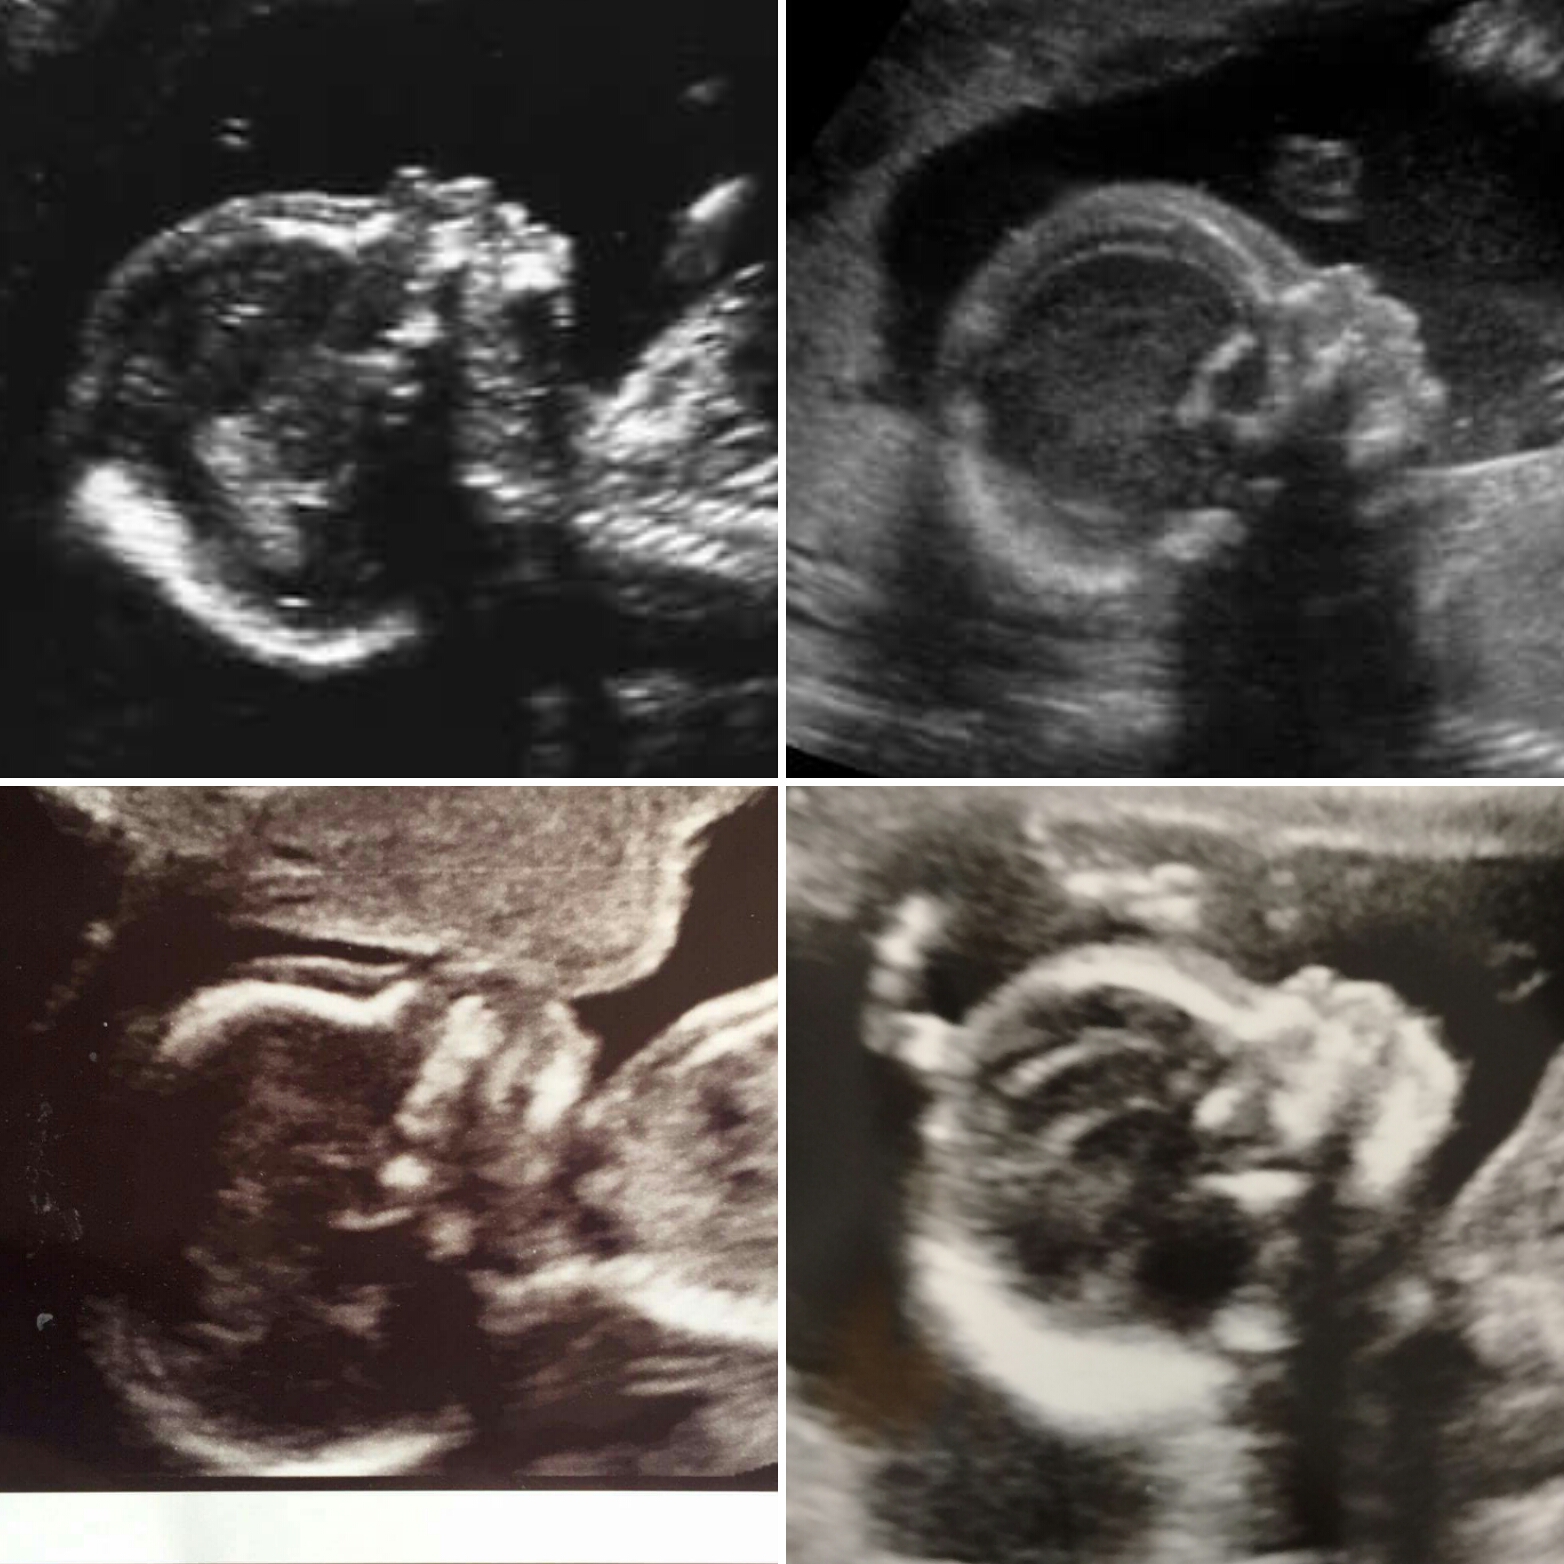

Posting for my best friend (mother of 3 boys and expecting again): 19w4d ultrasound of current pregnancy (top photo). Baby was being stubborn and kept its legs crossed! The bottom two pics are confirmed boys from previous pregnancies (older brothers). Any educated guesses of what this baby could be?? Thanks!